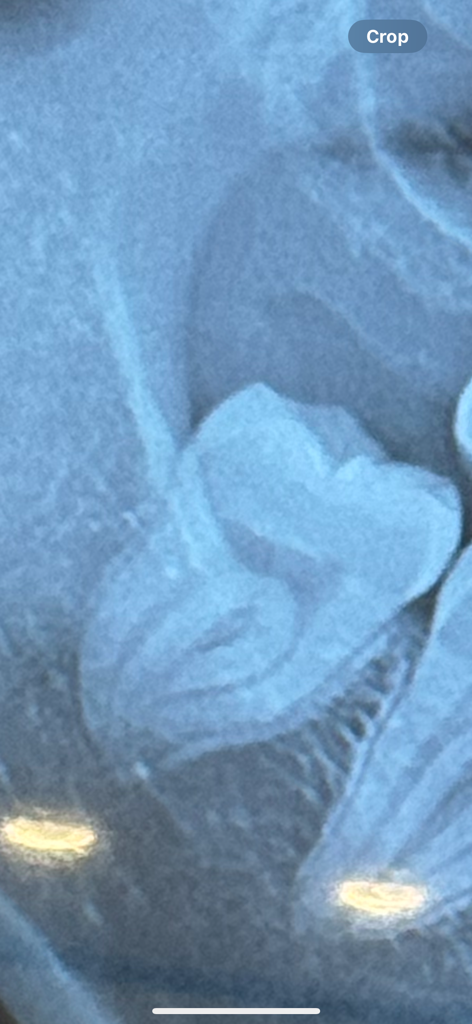

이렇게 생긴 사랑니 뿌리는 뽑을때 어려운가요?

제 사랑니는 이렇게 생겼는데, 안으로 약간 모여서 휘어있는듯 한데 일반 치과에서 뽑아도 되는건지 궁금합니다

(주변에서 사랑니는 전문병원 가라는 말을 많이 해서요ㅠ또 저런 뿌리 모양은 뽑을때 통증이 어떨지 궁금해요

1. 사랑니 뿌리가 아래턱 신경관과 근접합니다.

2. 사랑니 뿌리가 휘어져 있어서 발치 시 시간이 오래 걸릴 수 있고 뿌리 끝이 약간 부러져 뼈 안에 남을 수도 있습니다